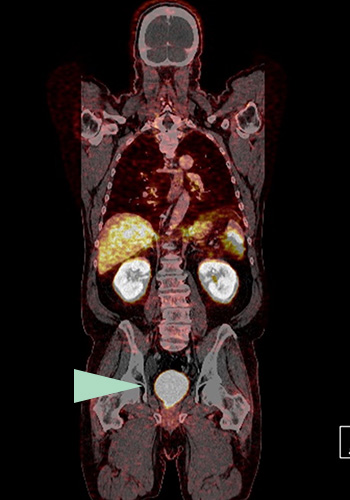

Prostatakrebs

Nachweis eines bisher unerkannten Tumorherdes (s. gelber Pfeil) durch das Fluor-18 PSMA PET-CT links hinter der Harnblase. Die Prostata war mehrere Jahre zuvor operativ entfernt worden. Ein PSA-Anstieg war der Anlass für die Durchführung des PET-CTs.

Mit dem F-18 PSMA PET-CT lassen sich kleine und kleinste Tumorherde und Absiedlungen des Prostatakarzinoms (Metastasen) in Lymphknoten und Organen nachweisen. Auch in der Prostata selbst oder in der Prostataloge wird Tumorgewebe sehr empfindlich detektiert.

Kleinste Tumorherde werden entdeckt (bessere Auflösung)

Tochtergeschwülste (Metastasen) im kleinen Becken und Tumore in der Prostataloge werden zuverlässig gefunden (da keine störende Anreicherung in der Harnblase erfolgt)